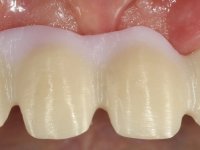

The patient did not like her smile, said that she had "very artificial looking teeth".

In view of the clinical situation, oral rehabilitation was proposed to improve the aesthetic appearance, but also to solve the lack of posterior teeth, seeking a functional and aesthetic rehabilitation. The plan included replacing the metal-ceramic bridge by a bridge with Zr infrastructure coated with coronary and gingival ceramics. The edentulous area of the first quadrant would be rehabilitated with 2 implants and a bridge of two elements. It was intended with this treatment plan, to recover the vertical dimension of the occlusion and to reshape the dental anatomy, thus creating a more natural aesthetic appearance.

Alginate impressions were made at both arches arcades, accompanied by intermaxillary registration relations and collecting information with facial bow facial bow. In the laboratory, a provisional bridge with 13 elements in autopolymerizable acrylic was built, in which a metallic reinforcement was included. Teeth 1.7 / 1.4 / 1.3 / 2.2 / 2.3 / 2.4 and 2.6 were used as pillars. The metal-ceramic bridge was removed after performing longitudinal cuts with diamond burs. The dental abutments were reprepared and the temporary bridge was relined in the mouth with self-curing acrylic. After confection of the provisional bridge, a gingival epithesis was made using composite resin with gingival tonality in order to function as a mock-up, which allowed the patient to preview the possibility of using gingiva shade ceramics in the final work. This option was approved by the patient. Subsequently, the placement of two implants in the first quadrant was planned and executed. The provisional monoblock was removed for placement of the implants, and after surgery was again cemented provisionally. After the osseointegration period, the impressions were made to the maxilla. In the anterior zone, impregnated gingival retraction cords were used, and in the posterior areas, kaolin paste was used. Implant printing utilized the open tray technique. The printing material used was soft and regular putty addition silicone, both fast-setting. In the laboratory, the model of provisional restorations and the gingiva epithesis mock-up served as orientation for waxing the infrastructure. The plaster work model and the waxing of the infrastructure were placed in a laboratory scanner and yielded a digital work model, in which the scanning of the waxed infrastructure was superimposed. This overlay facilitated the CAD design of the Zr infrastructure. Subsequently, the CAD drawing for a CAM milling process provided the Zr pieces. The infrastructure was pigmented with a pinkish coloration, which favors the subsequent placement of gum shade ceramic. During the modeling of the infrastructure, the need to increase the occlusal wear on tooth 1.4 was detected. This was done in the real working model cast and an acrylic wear control guide was created, which accompanied the proof of the infrastructures. Corrective wear and Zr parts test were performed in mouth. During the test, the color choice of the gum shade ceramic was reassessed. The treatment was finished in the laboratory, and after approval by the patient, was definitively placed in the mouth.